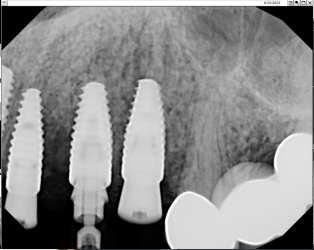

Treatment planning pt for implant bridge.

Im not sure if i should graft the 5 site and wait or place implant in 4 site and do mesial cantilever.